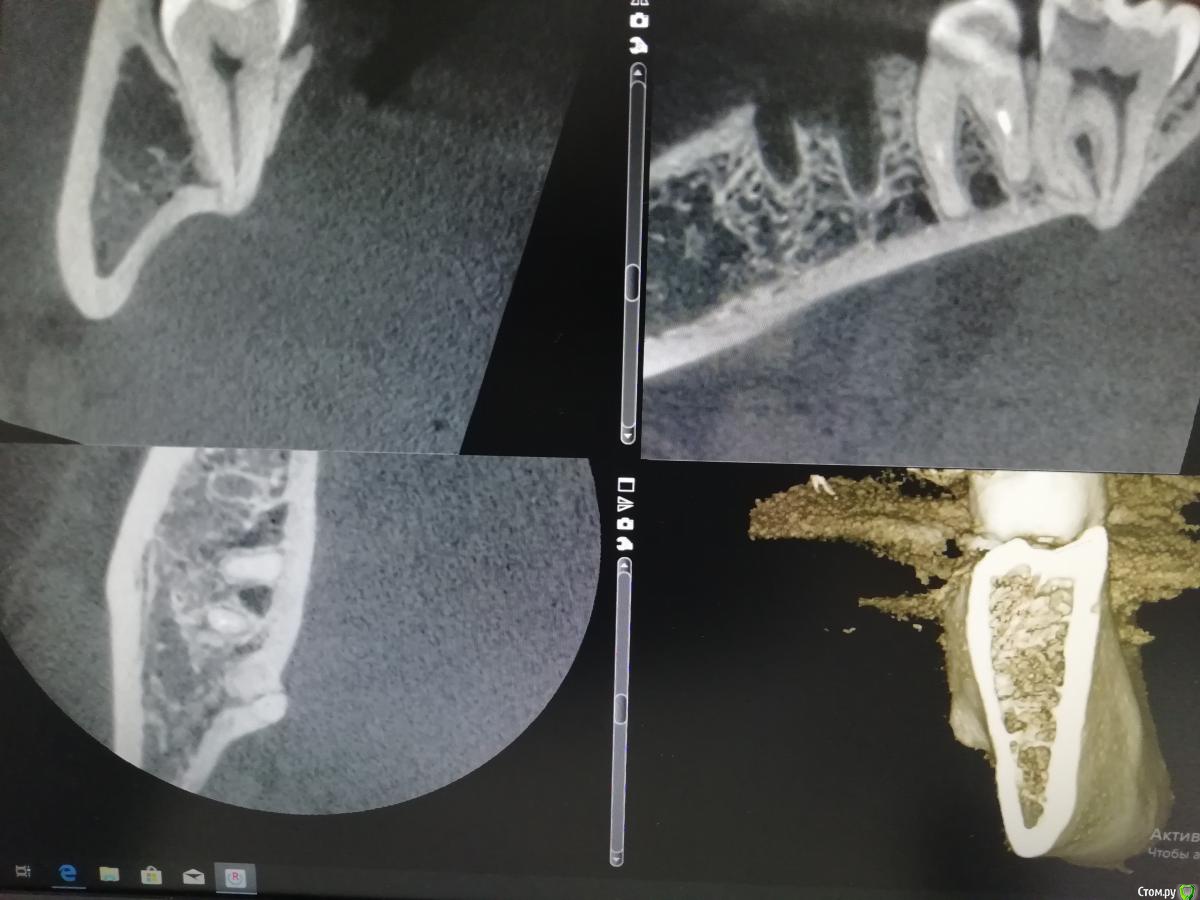

___49___ Опубликовано 10 декабря, 2019 Поделиться Опубликовано 10 декабря, 2019 Сегодня пришел другой вариант способный держать в тонусе, но уже на нижней челюсти ..... Ранее был опыт поиска апекса после проталкивания в поднижнечелюстное (обсуждали ситуацию , но без фото и Rg), кто-то спрашивал как это возможно - делюсь теперь уже задокументированным случаем (проталкивания в этот раз не было, но если бы удалять без КЛКТ, то вполне можно было бы и толкнуть ) 6 Ссылка на комментарий